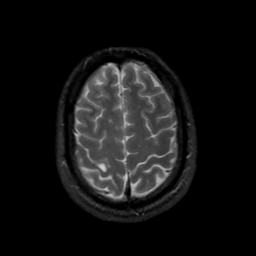

MR Study #13, May 19, 1991 -- Slice #41

[Home][Help][Clinical][Tour 1][Tour 2] Slice 41